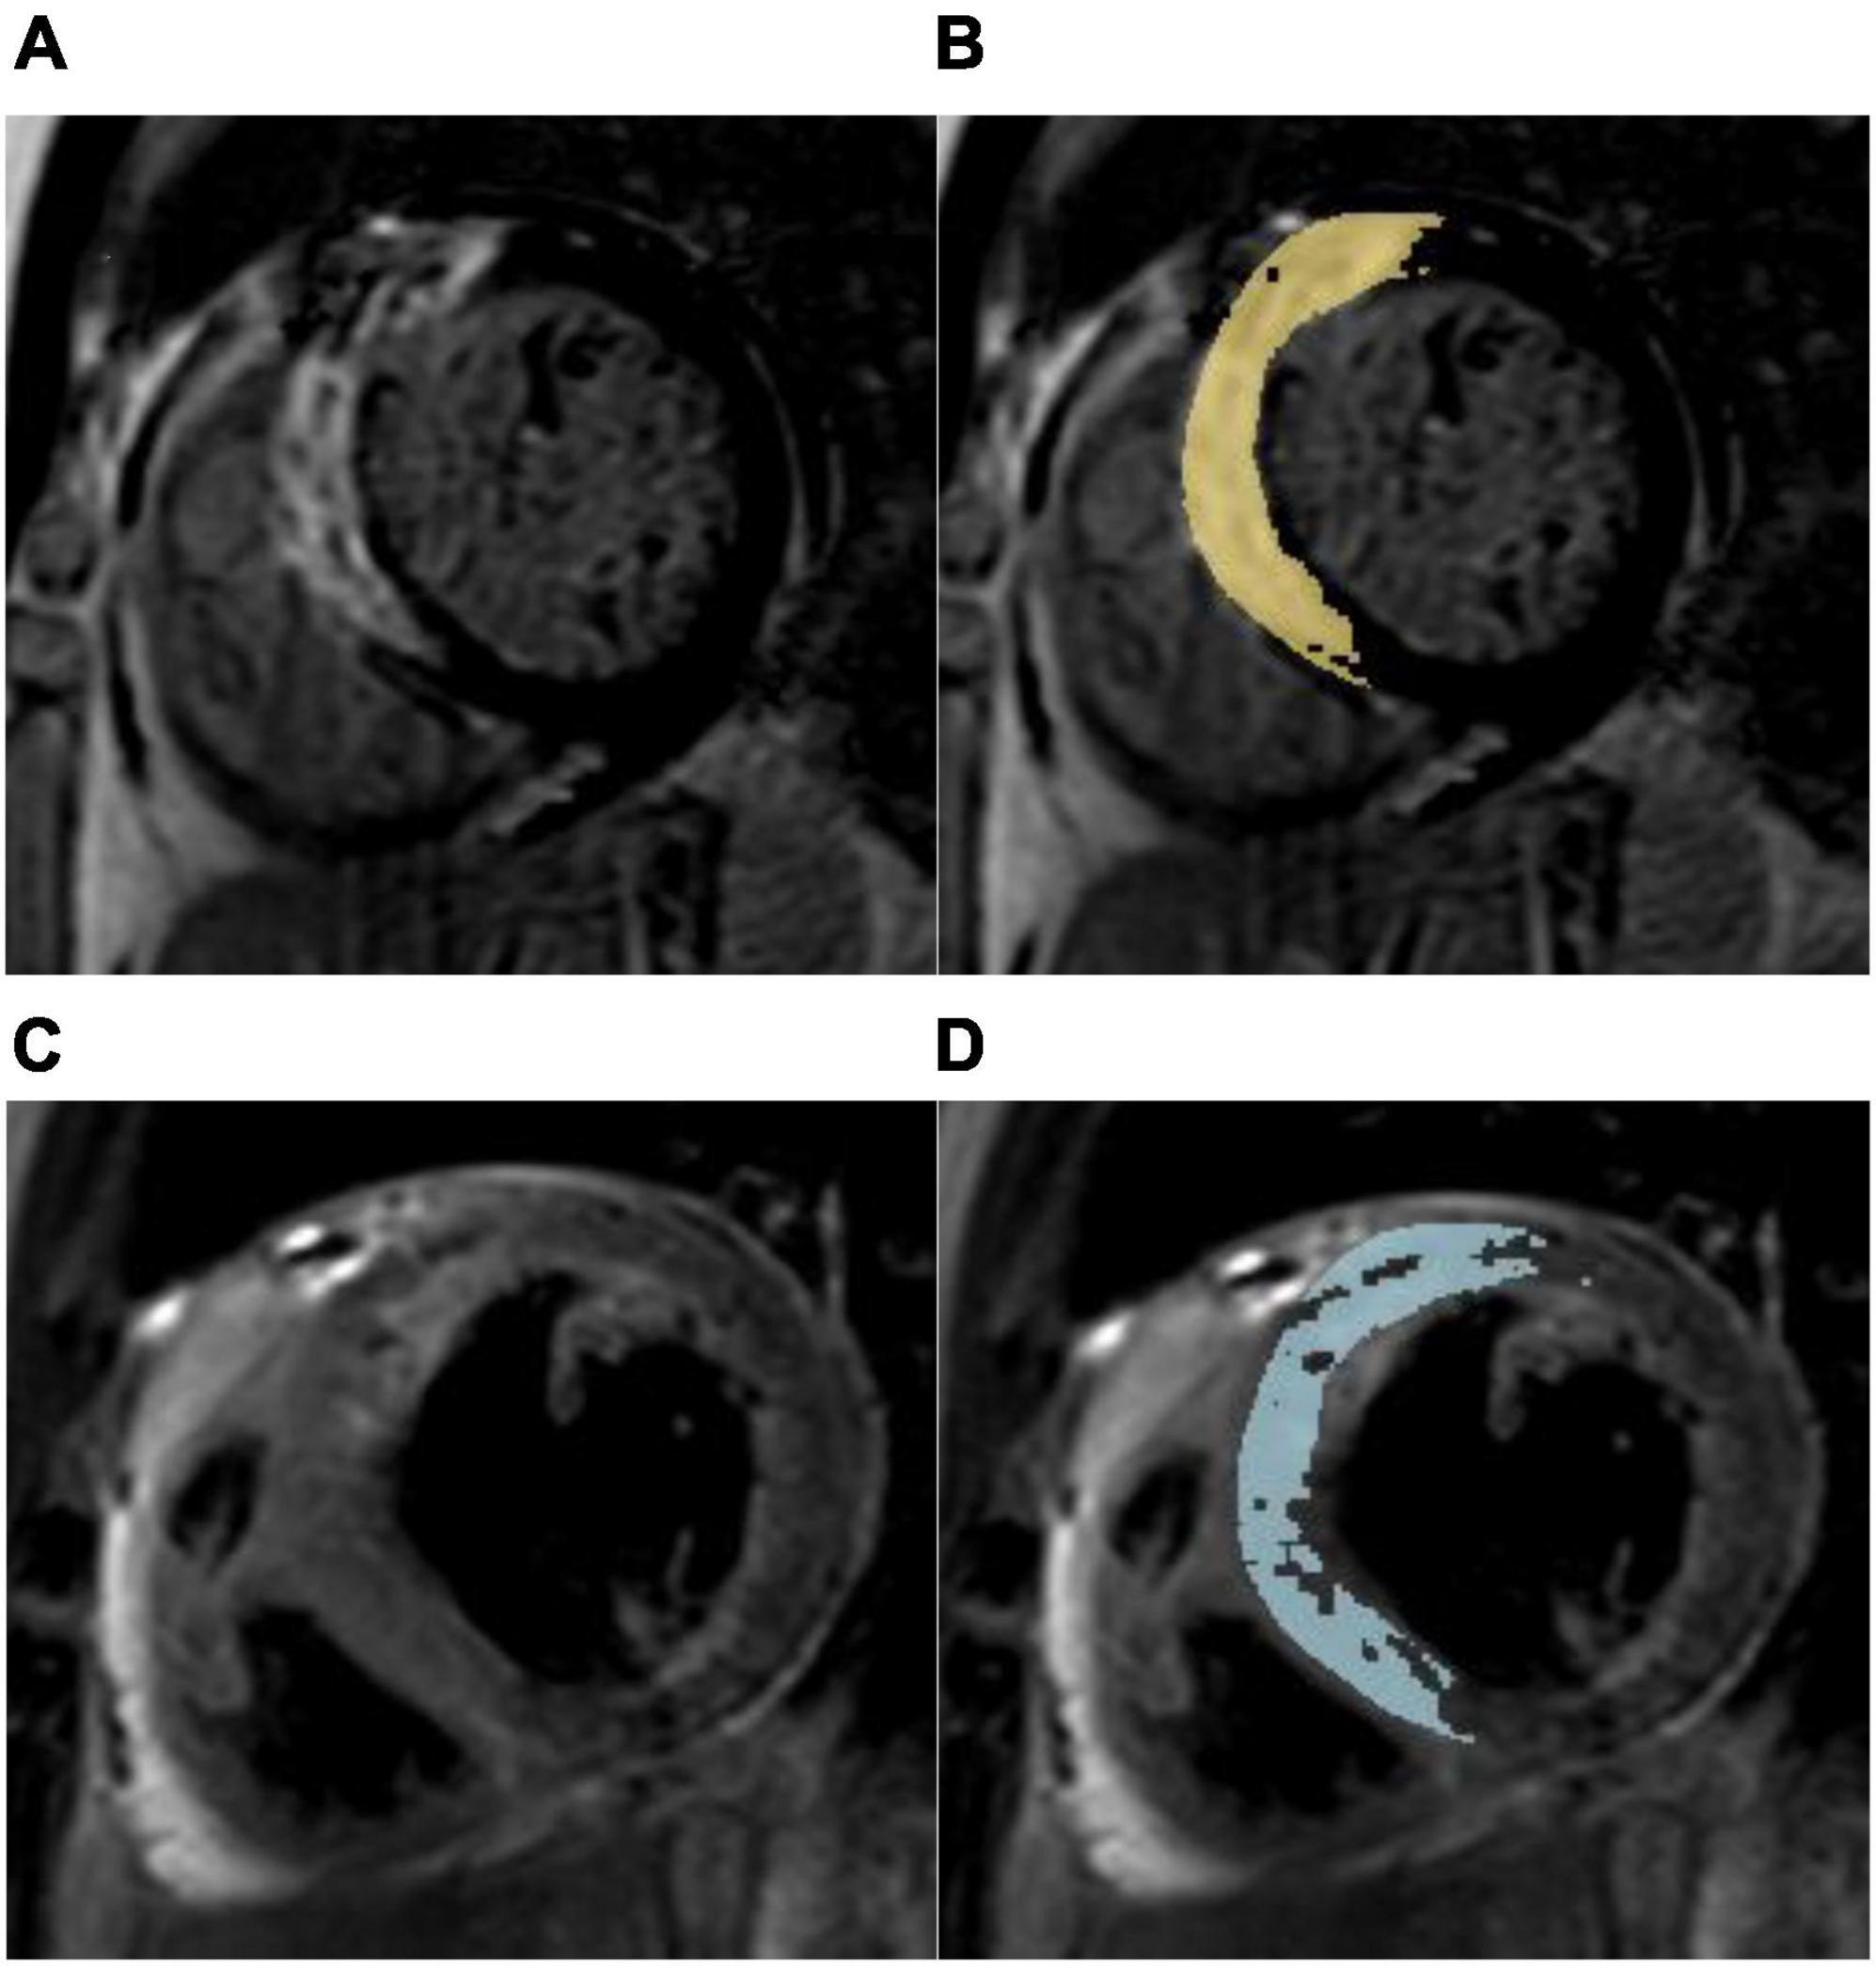

FIGURE 2

www.frontiersin.org

Figure 2. Myocardial salvage assessment in a 67-year-old male with a myocardial salvage index < median after acute reperfused myocardial infarction. (A) Representative short-axis late gadolinium enhancement (LGE) image showing a high signal intensity of the anterior, anteroseptal, and inferoseptal segments indicating myocardial necrosis. (B) Computer-aided signal intensity analysis of LGE image normalized to remote uninjured myocardium. The myocardial infarct size was 20.95%LV (left ventricle). (C) T2-weighted spectral attenuated inversion recovery image showing myocardial edema (area at risk) in the same region. (D) Computer-aided signal intensity analysis of the T2-weighted image normalized to remote normal myocardium. The myocardial area at risk was 34.30% LV, and the myocardial salvage index was 39.1. This patient with anterior myocardial infarction suffered non-fatal myocardial reinfarction and congestive heart failure during a 3-year follow-up.